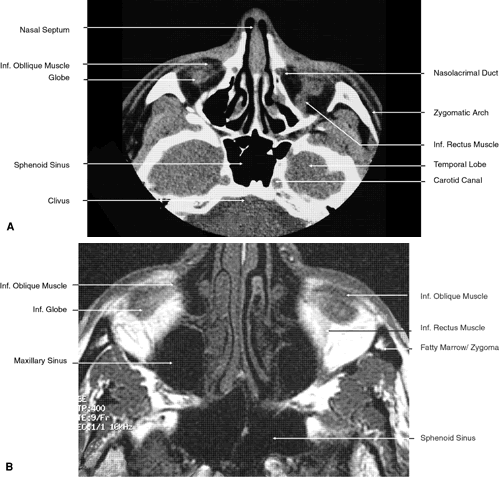

Fig. 22. Axial images at the level of inferior orbit. A. Computed tomography scan. B. T1-weighted magnetic resonance imaging.

Fig. 23. Axial images at the level of midorbit. A. Computed tomography scan. B. T1-weighted magnetic resonance imaging.

Fig. 24. Axial images at the level of superior orbit. A. Computed tomography scan. B. T1-weighted magnetic resonance imaging.